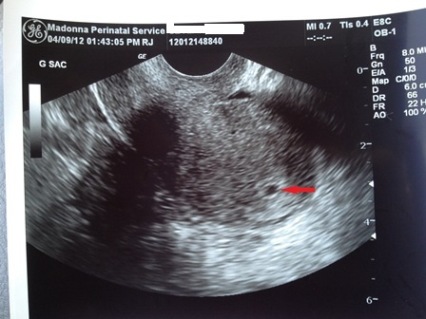

Things are looking up! I went in for another sono and blood test yesterday...we have a sac! Teeny tiny sac, but still a sac Heard from the OB today about my blood results and my beta is now up to 2800 and progesterone is at 8. It started at 1, then went to 2 on the second test, and now up to 8. Next visit is on the 17th

Image Attachment(s):